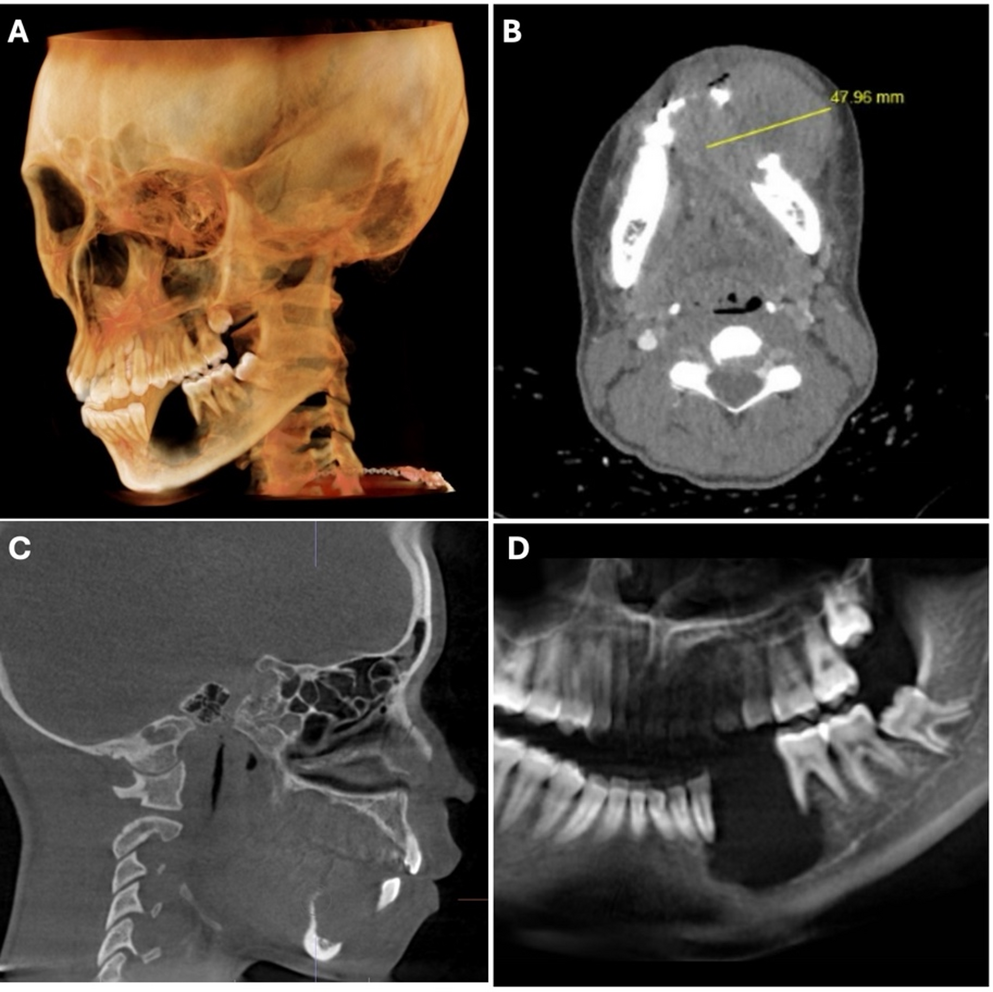

The patient had no significant medical history and not known drug allergies. Clinical examination revealed unilateral enlargement of the lower third of the face. The intraoral examination revealed a large, ulcerated mass on the right mandible, premolar area (Fig. 1). Teeth #20 and 21 are absent and adjacent #22 and #30 show class IV mobility. A scanned Cone Beam computerized tomography (CBCT) taken of the area of interest revealed a large radiolucency, of ~ 4.7 cm in diameter, in the left mandible around teeth #20 and 21, to include inferior displacement of the inferior alveolar nerve. Erosion of the buccal and lingual cortex is evident (Fig. 2).

Fig. 2

Radiographic presentation. A 3D rendition of Cone Beam Computerized tomography (CBCT). B Transverse view with measurement of the diameter of the lesion. C Sagittal view. D Portion of panoramic radiograph